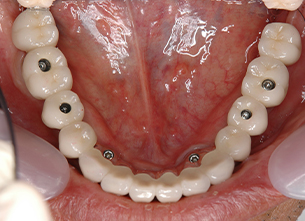

症例1 : 上下顎無菌顎症例

69歳、男性。

• 上顎は両側サイナスリフトと同時に即時荷重を行った。

• 下顎は抜歯即時埋入即時荷重を行った。

• 最終補綴物は、チタンのP.I.B.とM.B.のコンビネーションで修復した。

• 本症例の要旨は第39回日本口腔インプラント学会(大阪)にて症例報告した。